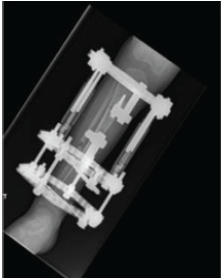

Impaired Bone Healing and Fracture Complications during Limb Lengthening in a Neurofibromatosis Type 1 Patient Receiving Selumetinib: Case Report and Literature Review

Zahra Safari , Maria Tirta , Ole Rahbek , Søren Kold

………………………………p.221-227